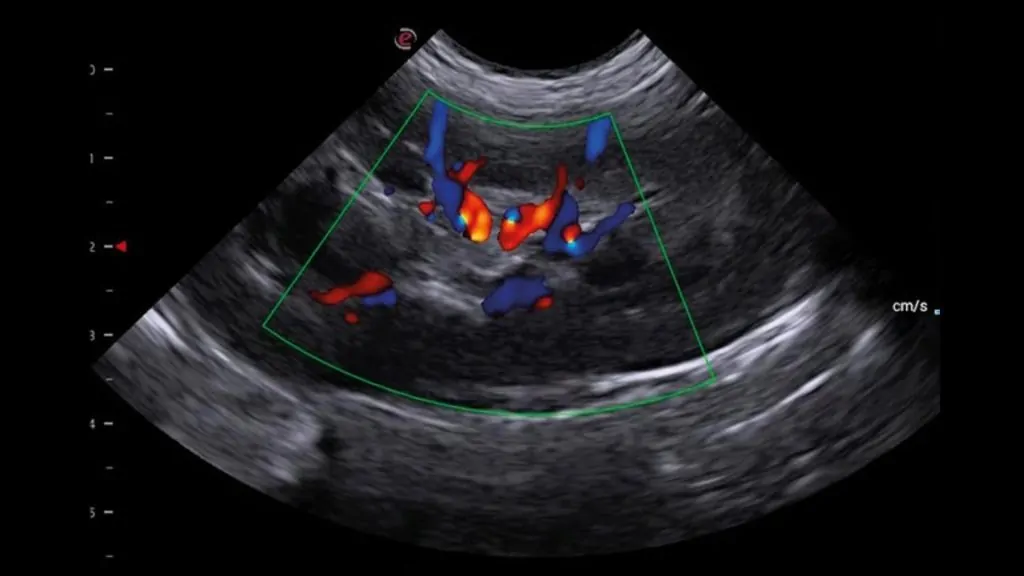

Ekokardiyografi; doğru tanı ve etkin tedavi yönetimi açısından büyük avantaj sağlar:

• Non-invazivdir: Ağrısızdır, güvenlidir ve çoğu hastada hızlıca uygulanabilir.

• Hızlı ve kesin yönlendirir: Kalp hastalıklarında tanıya giden yolu netleştirir.

• Tedavi planını güçlendirir: Hastalığın şiddeti ve kalp fonksiyonlarına göre en uygun tedavi yaklaşımının belirlenmesine yardımcı olur.

• Prognoz belirlemede kritiktir: Hastalığın seyri ve yaşam kalitesine etkisi hakkında güçlü öngörü sağlar.

• Takipte standarttır: Tedaviye yanıtın izlenmesi ve ilerleyişin kontrolünde vazgeçilmezdir.